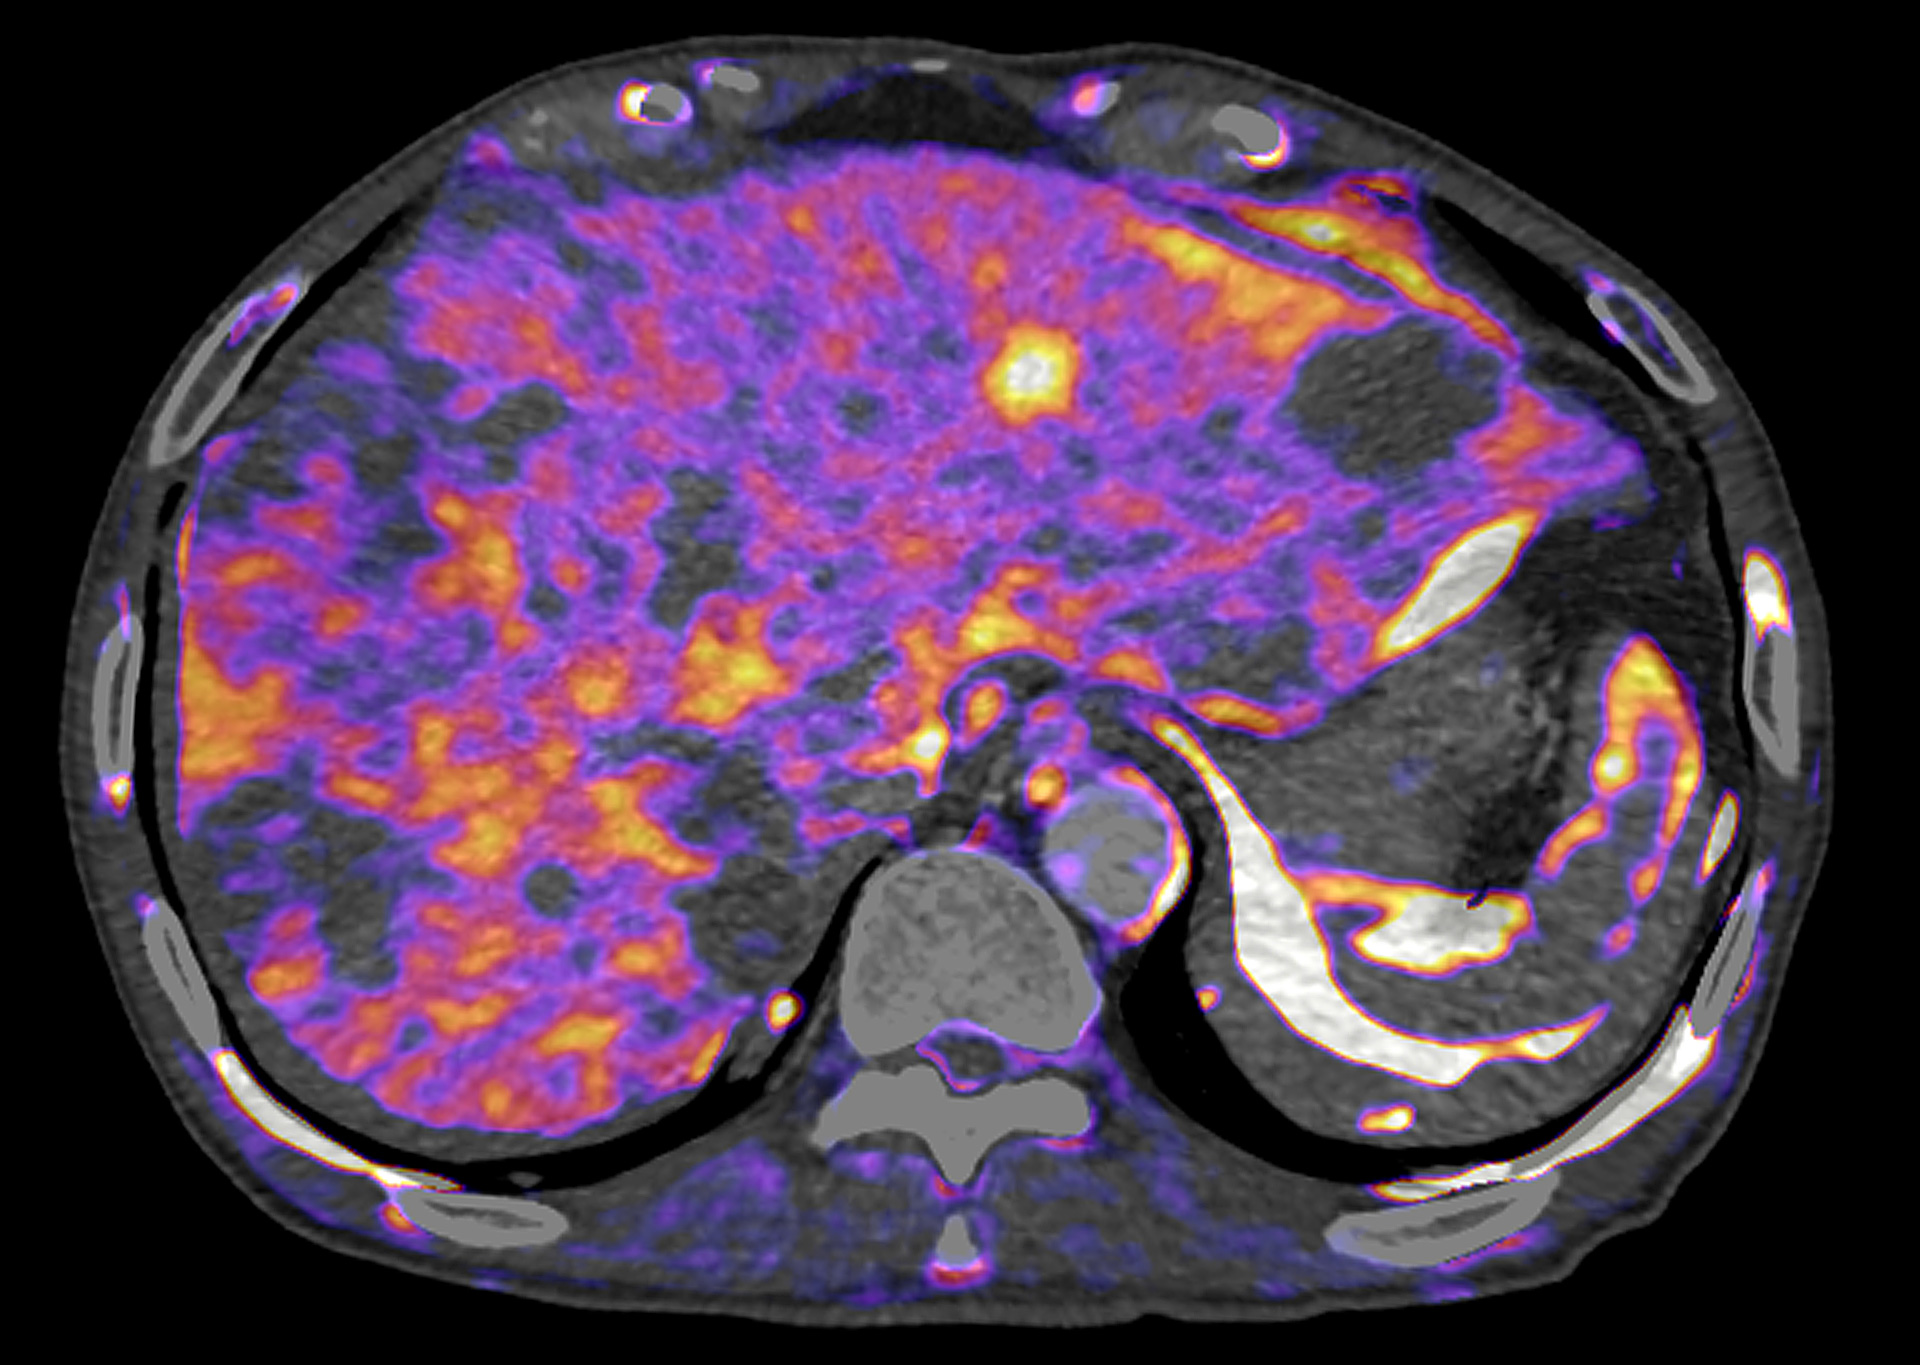

CT Body Perfusion 4D

CT Body Perfusion 4D enables whole organ functional assessment. Parametric maps, based on the contrast flow through an organ, provide additional information to aid clinical decision-making.